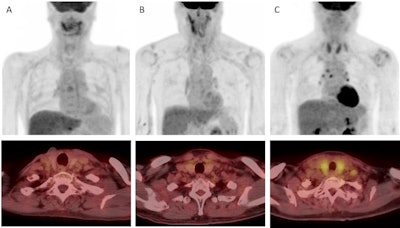

First, the researchers visually assessed thyroid uptake on PET/CT. Two patients (4%) had diffuse thyroid uptake (visual grade 3), 32 (62%) had visual grade 2 uptake, and 18 (35%) had visual grade 1 uptake. The two patients with visual grade 3 uptake later developed hypothyroidism.

Next, a quantitative analysis of thyroid functioning volume revealed that F-18 FDG radiotracer uptake was significantly lower in patients who developed hypothyroidism than in those who did not (10.61 cm3 versus 16.30 cm3, p < 0.001).

Lastly, a clinical algorithm that combined visual grading of thyroid uptake combined with a thyroid functioning volume capped at 14.01 cm3 predicted late-onset hypothyroidism with an area under the curve value of 0.89, according to the findings.